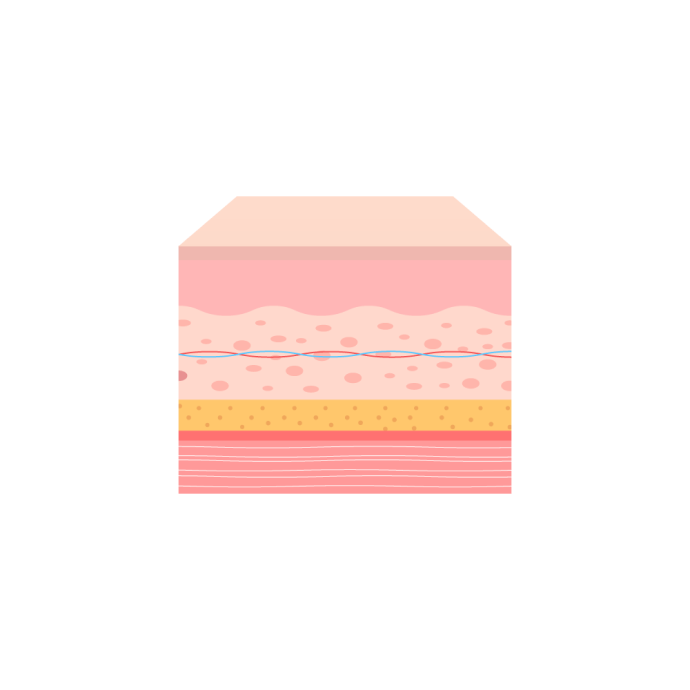

การฟื้นฟูด้วยสเต็มเซลล์

กำจัดไขมัน แต่คงไว้ซึ่งสเต็มเซลล์!

การดูดไขมันอย่างปลอดภัยที่คงไว้ซึ่งสารกระตุ้นการเจริญเติบโตภายในสเต็มเซลล์

ที่ The LINE เราได้รวมทุกสิ่งไว้ในขั้นตอนการดูดไขมัน

ผลลัพธ์ที่น่าทึ่ง การฟื้นตัวที่รวดเร็วขึ้น สุขภาพร่างกายที่ดีขึ้น และการเปลี่ยนแปลงอย่างน่าประทับใจ